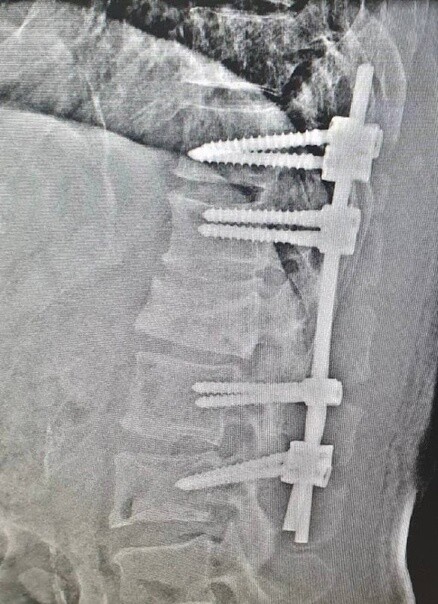

Метастазы в поясничном отделе: диагностика и лечение